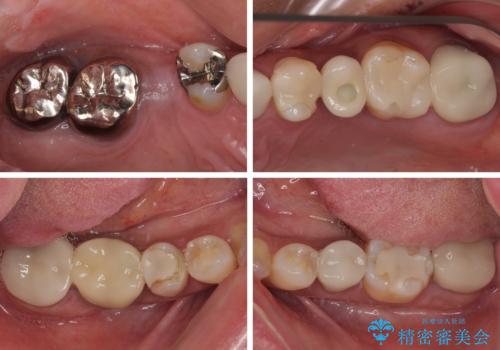

- 地元の歯科医院で治療を行っていたものの、難しいので都会に行くように指示をされたとのことで来院された患者様です。

右下のむし歯が歯肉縁下に及んでおり、歯周外科処置(歯冠長延長術)を行った上で、根管治療を行い、状態を整えて補綴治療を行うこととしました。